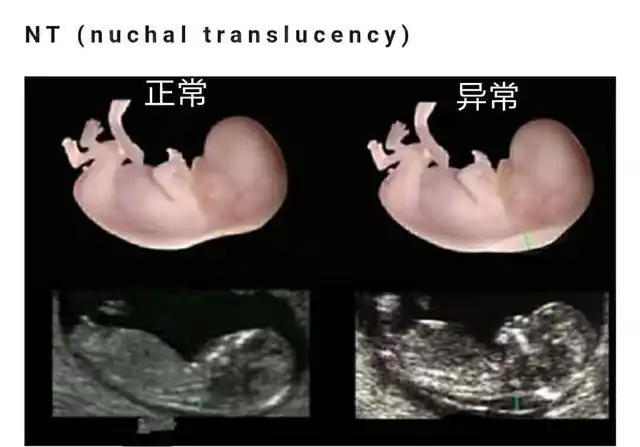

怀孕3个月男女胎儿差异大:4件小事孕妇要常放在心上,尤其第1件